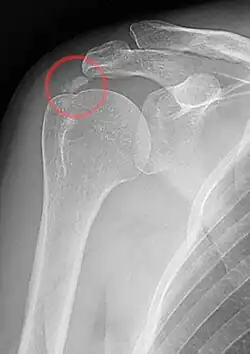

Röntgenbild einer Kalkschulter

Die Diagnose wird gestellt durch Schulterschmerzen, die auf eine „Verkalkung“ in der Rotatorenmanschette zurückzuführen sind. Die Schmerzen treten spontan ohne Trauma auf oder nach vermehrter Überkopftätigkeit (Impingement). Die „Kalkdepots“ bilden sich in den Sehnen kurz vor dem Ansatz der Rotatorenmanschette am Oberarmkopf, meist am Supraspinatus, seltener am Infraspinatus und Subscapularis. Stärke und Dauer der Beschwerden hängen vom Stadium der Erkrankung ab. Mehrere „Kalkdepots“ gleichzeitig sind nicht selten. Im Röntgenbild sind die „Verkalkungen“ gut zu erkennen und haben je nach Krankheitsphase ein unterschiedliches Erscheinungsbild.

Im Röntgenbild sind die „Verkalkungen“ gemäß der Stadien gut zu erkennen. In der Kalzifikationsphase erscheint die „Verkalkung“ dicht, homogen und scharfrandig und kann über Jahre an Größe zunehmen (Typ I). In der Resorptionsphase findet man eine transparente und unscharf begrenzte Struktur, die oft großflächiger und inhomogen erscheint (Typ III). Beim Typ II zeigt das Röntgenbild gemischte Strukturen und kann nicht sicher zugeordnet werden.[6] Etwa drei Monate nach Beginn der Resporptionsphase ist die „Verkalkung“ im Röntgenbild nicht mehr erkennbar. Gut stecknadelkopfgroße Restverkalkungen können verbleiben, bereiten jedoch keine Probleme mehr.